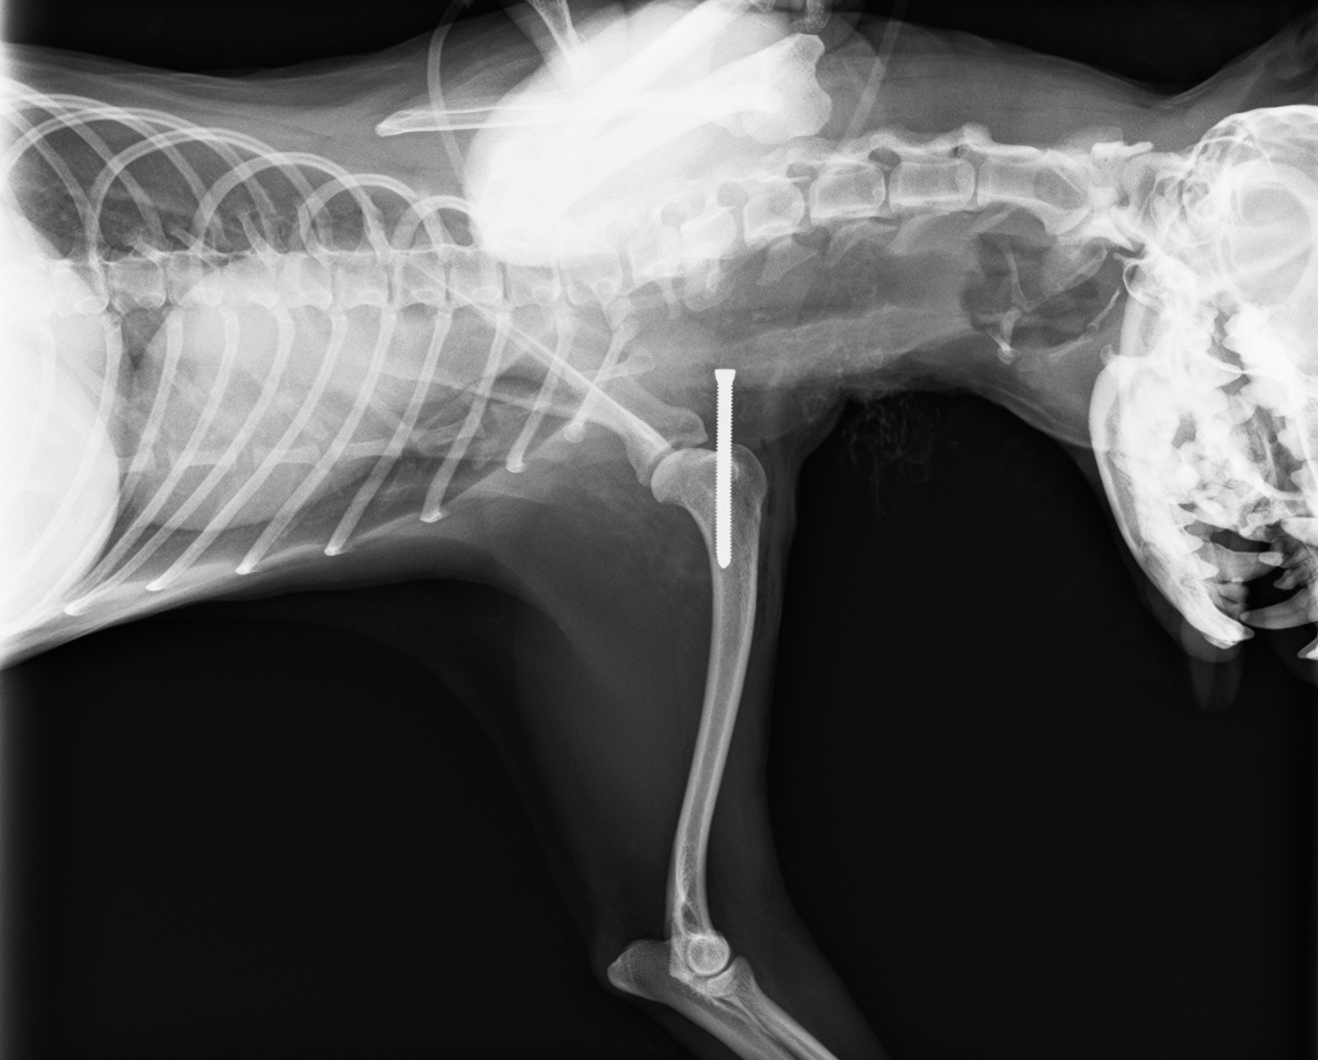

レントゲン検査より、右肩関節脱臼

診断と治療

右肩関節脱臼と診断し、スクリューを上腕骨に挿入し、肩関節を安定化させる

before